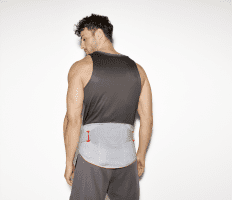

Rückenorthese Cellacare Lumbal Classic schwarz-grün

Artikelnummer:

500768

Hersteller:

Lohmann & Rauscher GmbH&Co.KG

LWS-Orthese VERTEBRADYN STABIL platinum

Artikelnummer:

500438

Hersteller:

Sporlastic GmbH

LWS-Orthese VERTEBRADYN AKTIV mit Propriozeptionspelotte, platinum

Artikelnummer:

500439

Hersteller:

Sporlastic GmbH